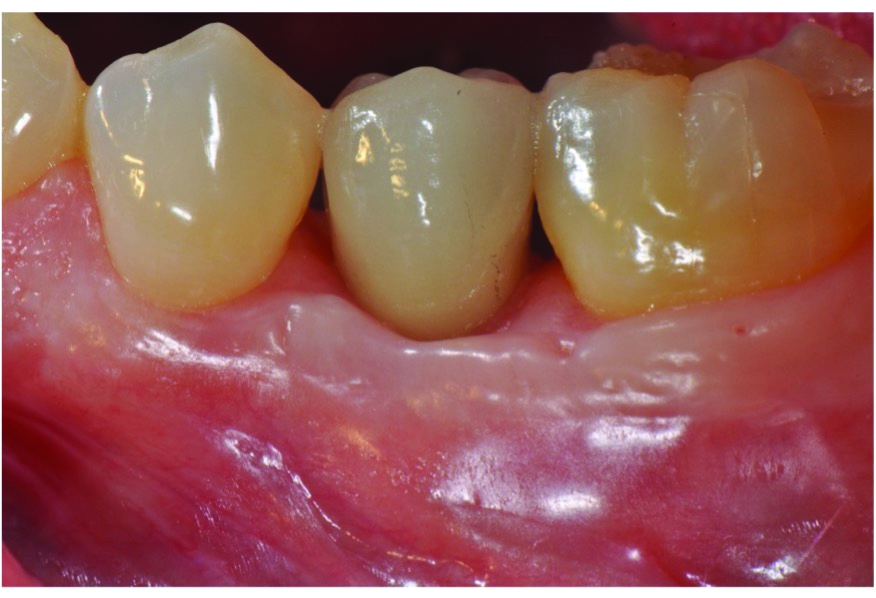

At 5 years post-implant placement, implant site No. 20 showed circumferential depths of 6 mm to 8 mm with heavy bleeding on probing (Figure 1).1,47 The keratinized mucosa width locally recorded 4 mm buccally and lingually, with a thick gingival phenotype. The four-wall intrabony lesion was diagnosed as a class 1c (circumferential) intrabony peri-implant defect with less than 40% defect angulation in the mesial and distal radiographic aspects (Figure 2).48 Additionally, resin cement-associated peri-implantitis was diagnosed.49 The patient preferred to maintain the existing well-fitting crown due to financial concerns. The patient would be considered low-medium risk according to the PIDRA (Table 3). (To view Table 3, the PIDRA for this case, visit compendiumce.com/go/2505.)

Fig 1. The patient presented with a probing depth of 6 mm to 8 mm at site No. 20 and bleeding on probing.

Figure 1